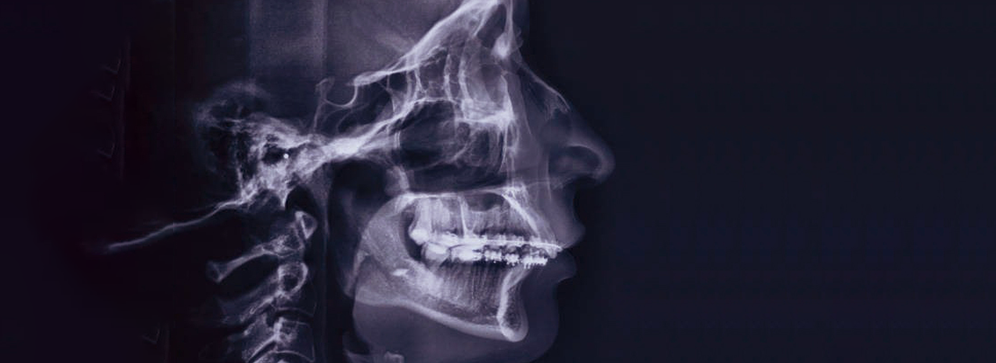

Lateral cephalometry is a highly specialized dental and orthodontic imaging technique that captures a complete side-view image of the skull, jaw, and facial bones. Unlike regular dental X-rays that focus mainly on the teeth, lateral cephalometry provides a broader perspective, allowing orthodontists, oral surgeons, and dentists to assess the relationships between different facial structures. This type of imaging is essential for planning orthodontic treatments such as braces or aligners, preparing for corrective jaw surgeries, monitoring facial growth in children, and even diagnosing airway-related conditions like obstructive sleep apnea. The image provides accurate angular and linear measurements that guide precise treatment decisions.

Lateral cephalometry is a diagnostic X-ray that captures a side profile of the head, showing the bones and facial contours in precise detail. It allows dentists and orthodontists to evaluate how the jaw, teeth, and skull relate to one another in terms of position, proportion, and alignment. This information is crucial when deciding whether a patient needs orthodontic appliances, surgery, or other corrective treatments. It is also invaluable in tracking changes over time, such as jaw growth in children or treatment progress in orthodontic cases.

The lateral cephalometric image is more than just a picture; it is a tool for measurement and analysis. Orthodontists can use specialized software to analyze the image, measure bone angles, assess airway size, and predict how treatments will affect facial appearance. Because of its ability to show both hard and soft tissues, it provides a holistic view of the patient’s craniofacial structure. This makes it a key diagnostic tool in modern orthodontics and maxillofacial surgery.